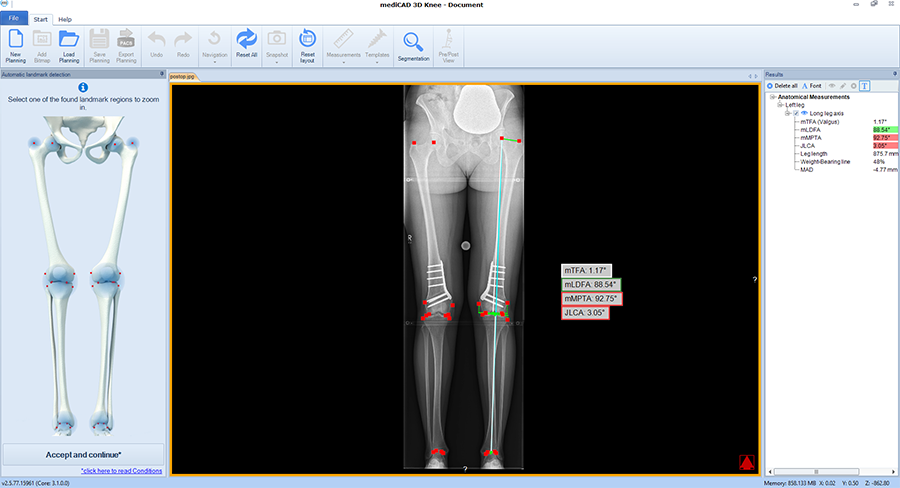

The software automatically detects all necessary landmarks (Fig 1). Based on their position (which can be adjusted manually) the software calculates all essential values (axis, joint lines, and angles) and delivers a detailed report. A traffic light system illustrates normal, intermediate, or pathological values.